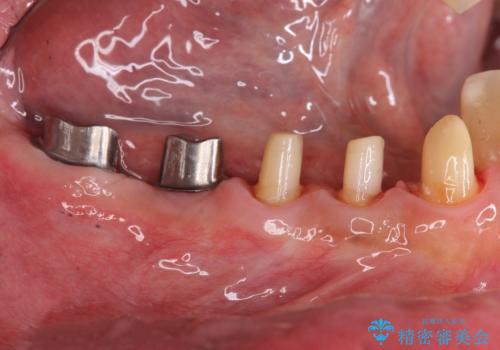

多数の銀歯と虫歯、セラミック・インプラント治療

- 銀歯だらけの口腔内を全てきっちり治療したい、と希望され来院されました。

検査の結果、残すことの難しい歯をインプラントに置き換え、残すことのできる歯は虫歯の徹底的な除去後にセラミック治療を行っていくこととしました。

銀歯が口腔内からなくなり審美的になっただけでなく、歯ブラシのしやすさや噛み合わせの安定、口臭の減少など、良好な結果を得ることができました。